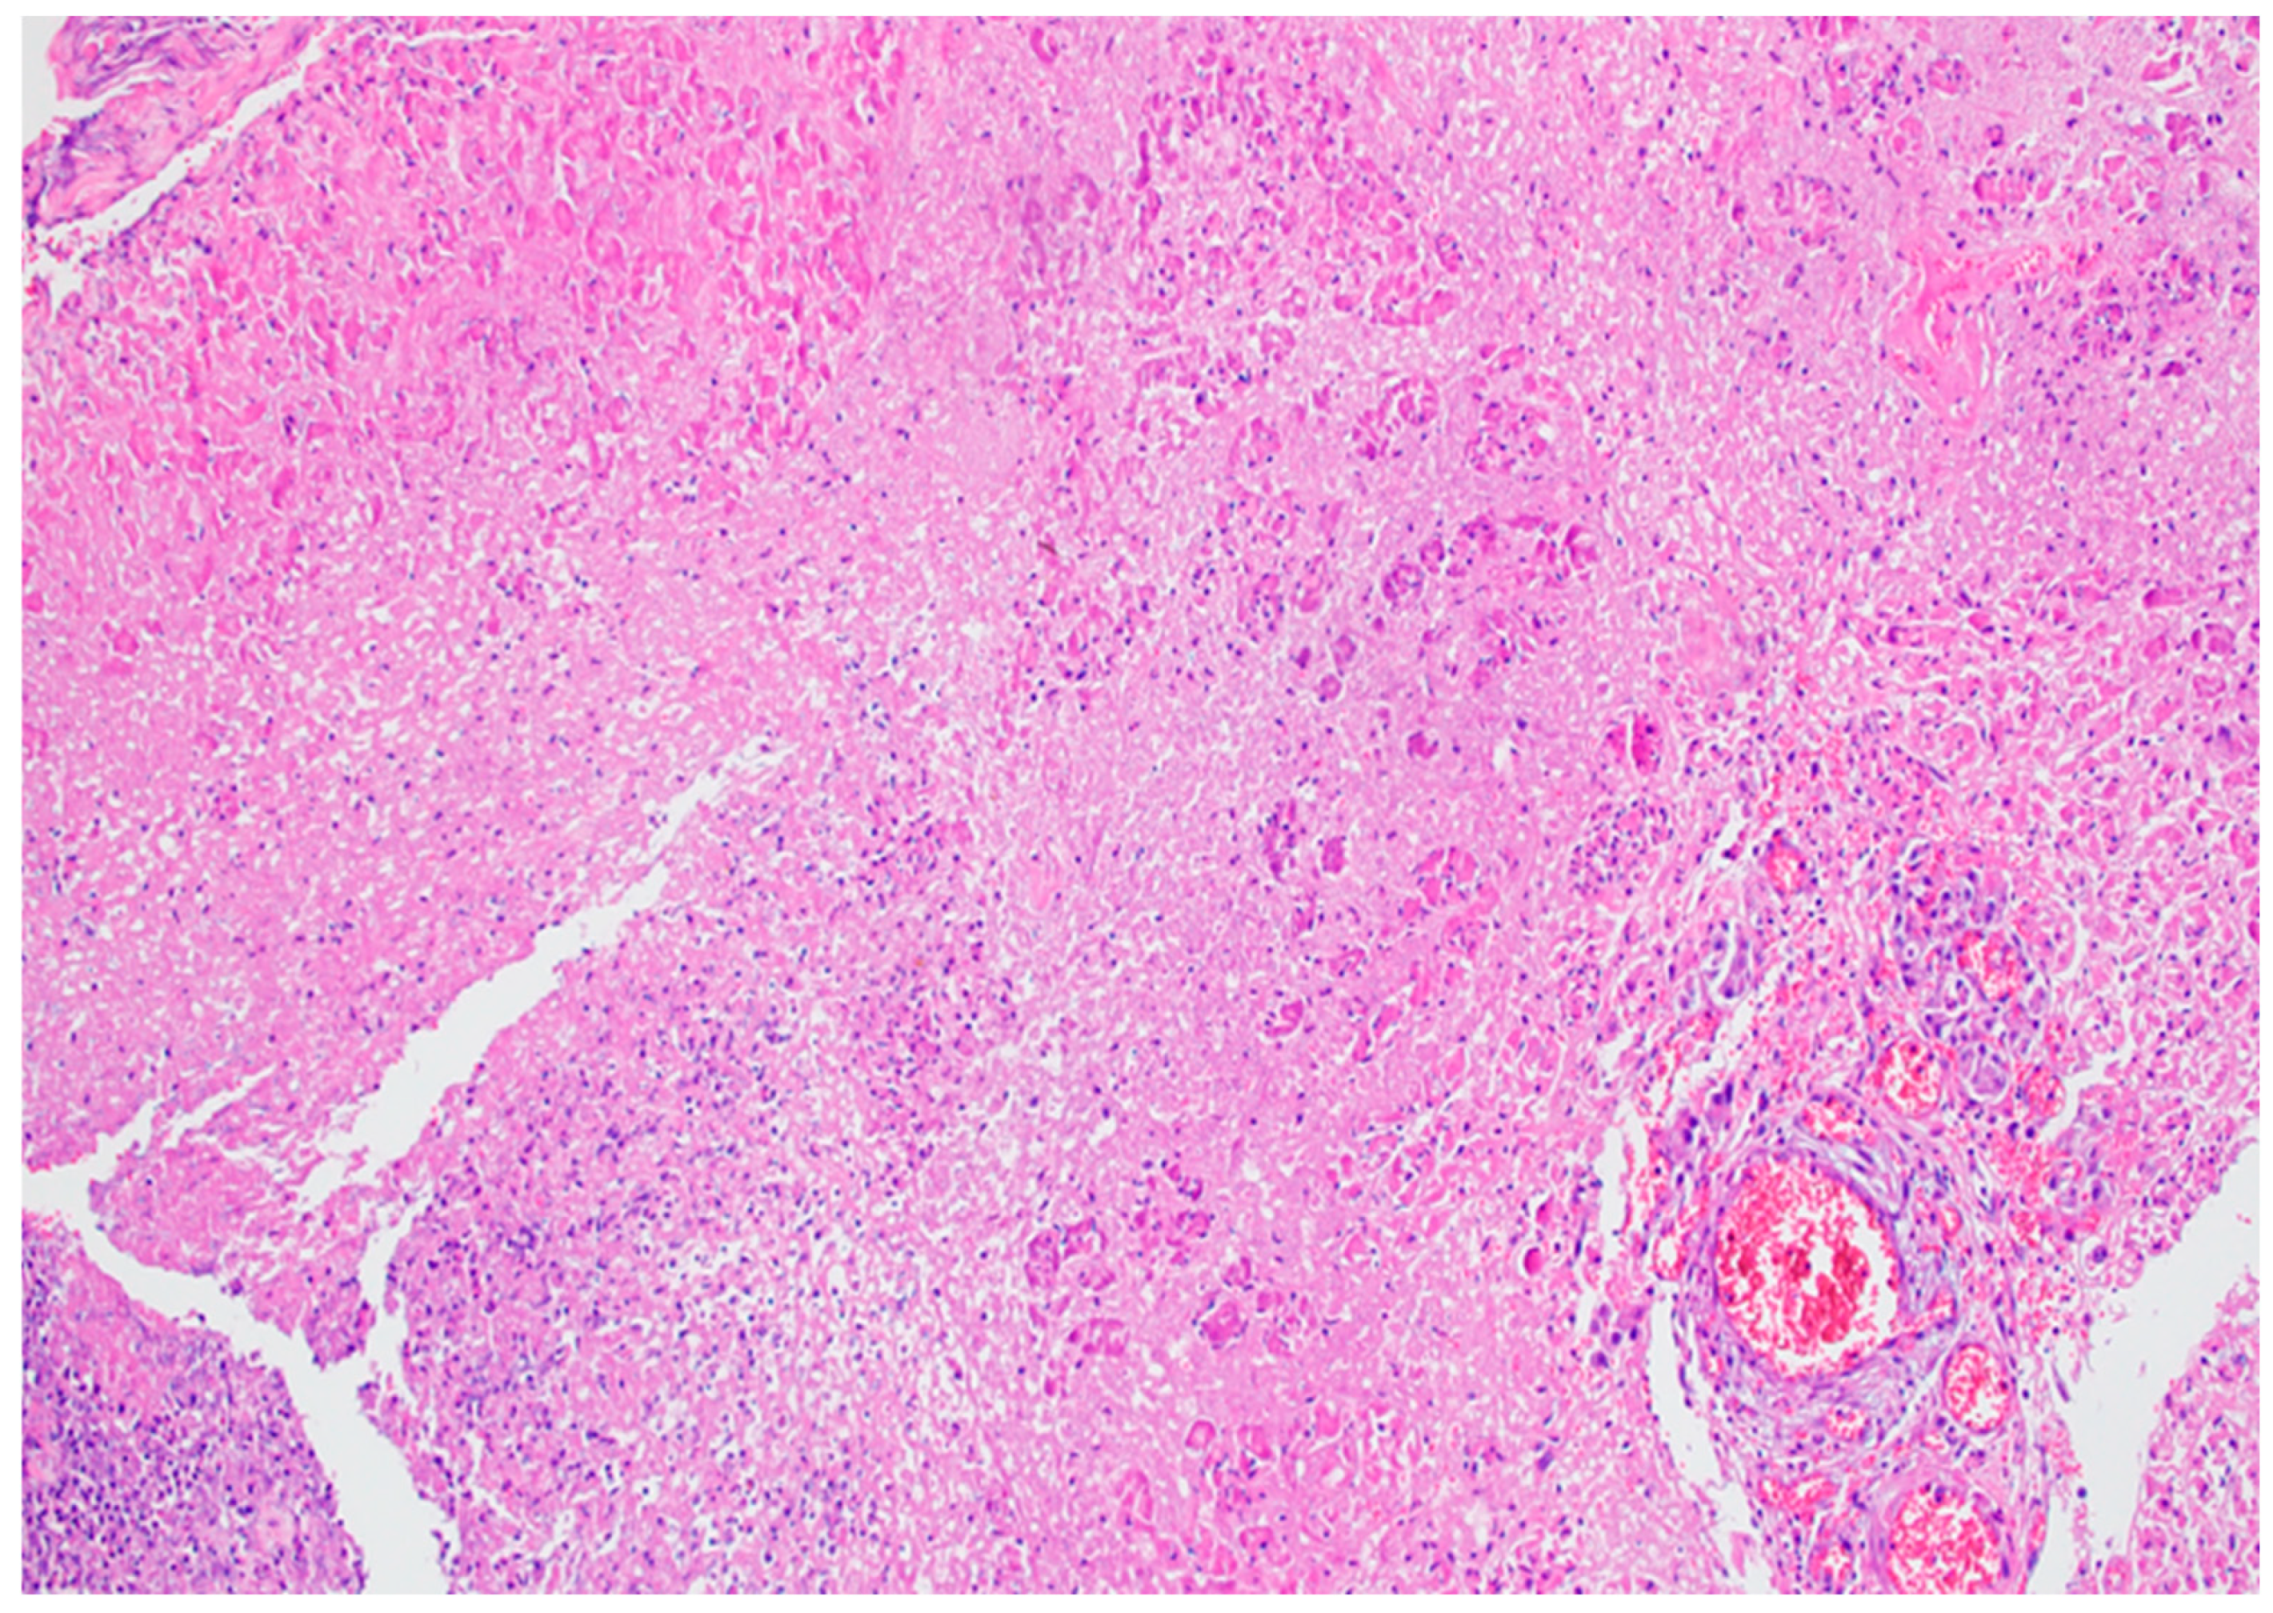

5. Histopathology of Acute Pancreatitis